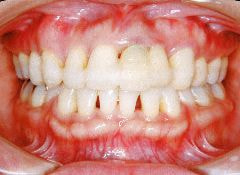

治療例2 (補綴処置+矯正)